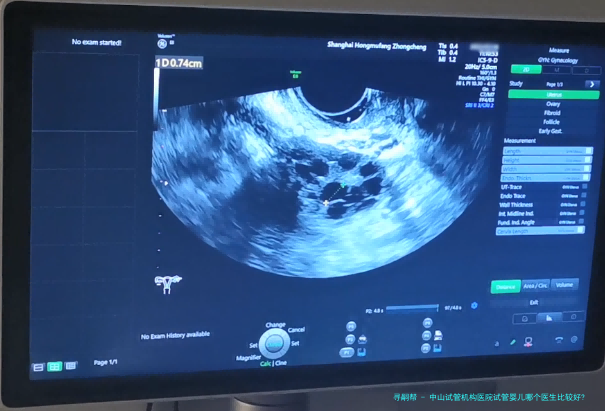

胚胎培养:将促排卵后的卵子和精子在实验室进行受精和培养,待胚胎发育到5-8个细胞期后进行移植评估。 宫颈检查:使用超声刀对宫颈进行观察和检查,确保宫颈健康状况良好。 胚胎移植:将优质胚胎经阴道或子宫腔内种植到女性子宫内。 移植后恢复期:患者需保持充分休息,避免剧烈运动和性生活,并接受药物治疗以提高妊娠成功率。